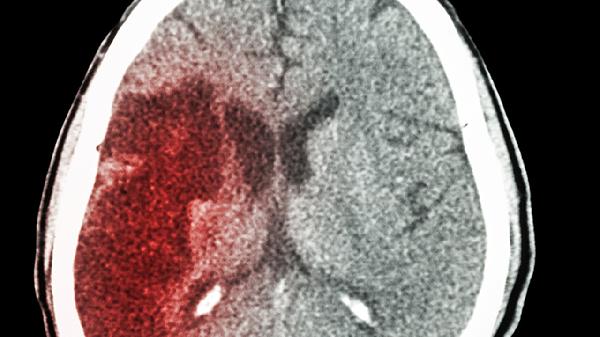

脑出血量直接影响脑组织损伤程度。30毫升以下的出血经及时手术清除后,神经功能代偿空间较大;超过50毫升的出血可能遗留永久性功能障碍,需通过高压氧治疗和神经修复药物促进恢复。

癫痫是常见远期并发症,需长期服用丙戊酸钠预防发作。脑积水患者可能需行脑室腹腔分流术,定期复查CT监测颅内压力变化。抑郁情绪可通过认知行为干预改善。